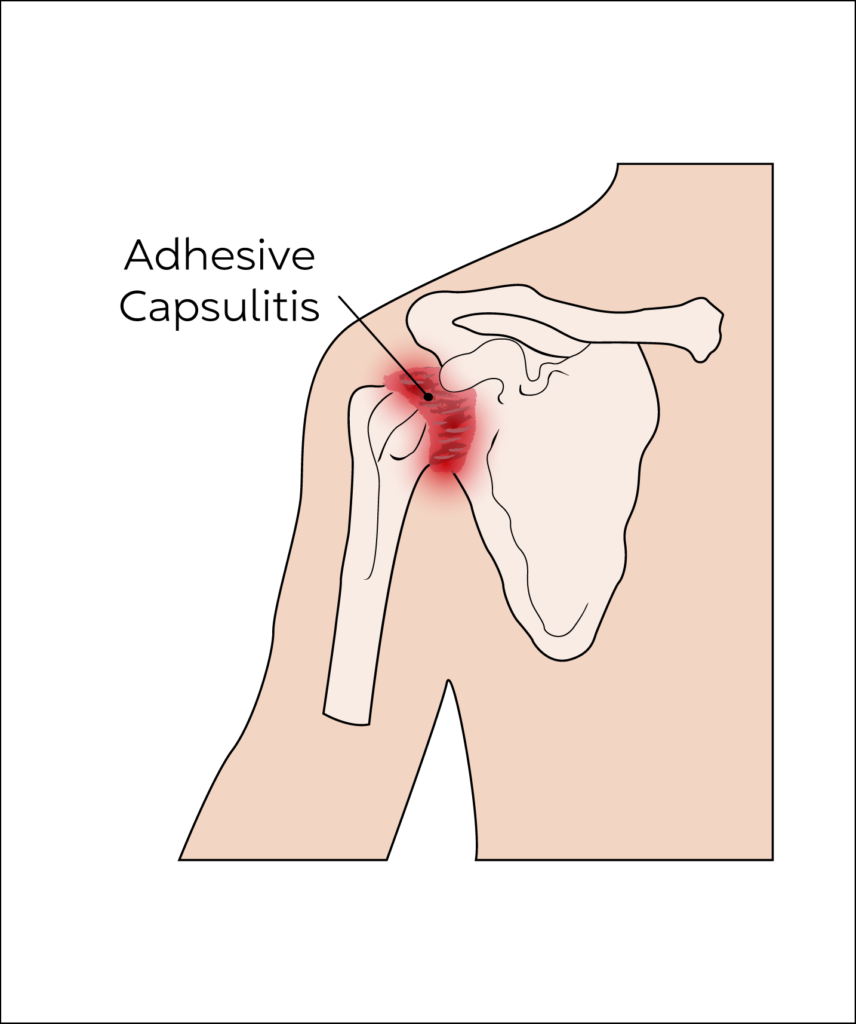

Adhesive Capsulitis - Frozen Shoulder

The covering of shoulder joints known as the capsule gets thickened, inflamed and scarred, which results in pain and restricted movement of the shoulder joint. Pain is usually worse at night affecting sleep and can radiate into the arm and/or neck.

Frozen shoulder affects 2% to 5% of the population with 1 in 5 developing the condition in both shoulders. It occurs more commonly in women and patients with diabetes.

Pain and restriction of movements are the predominant presenting complaint. Pain is usually worse at night restricting sleep, waking them up at night and can radiate into the arm and/or neck.

Ultrasound guided injection into the joint using corticosteroid and local anaesthetic are an effective method of getting short term pain relief so that individuals can engage with physical therapy and rehabilitation. Another modality of treatment offered here at Rejuvence Clinic is Hydrodistension.